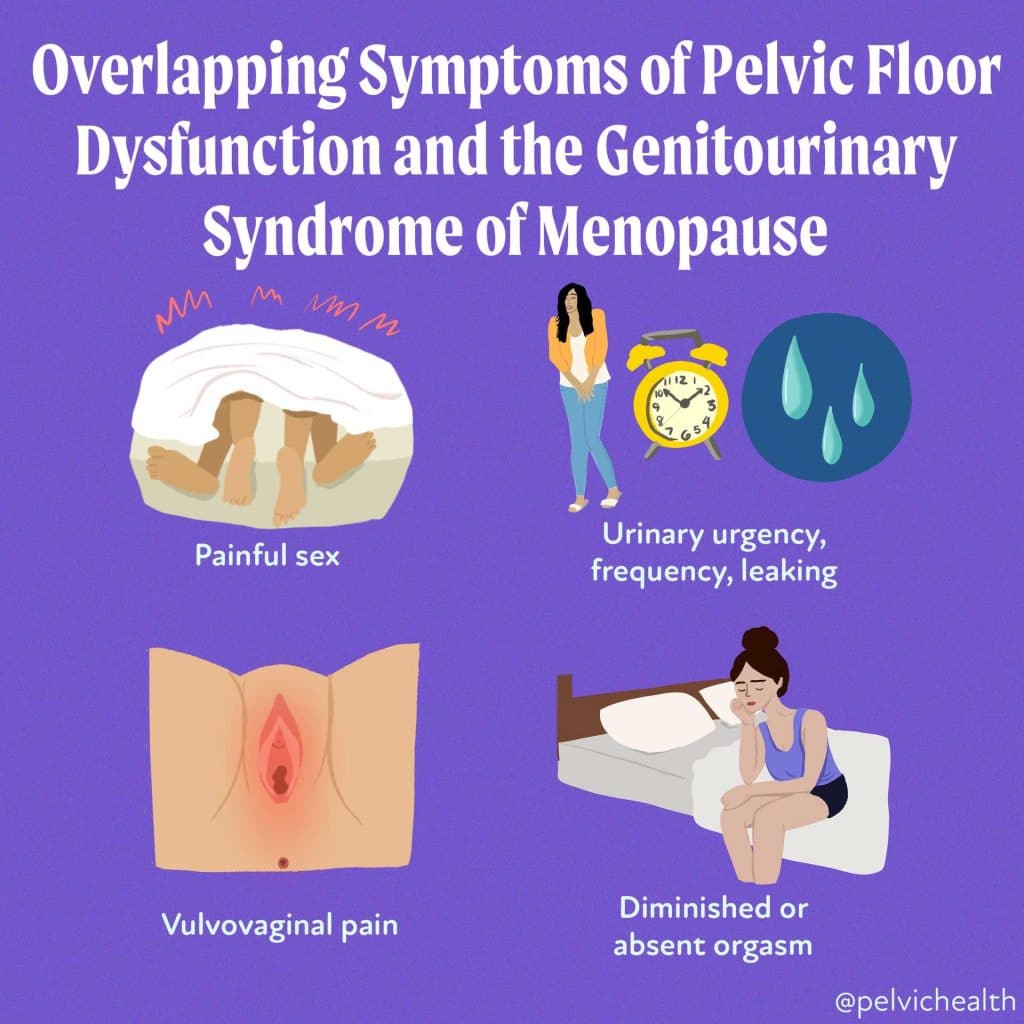

Menopause is more than just hot flushes, night sweats and mood changes! Even though 50% of the population goes through menopause the majority of people and healthcare providers are under-informed about menopause and safe and effective treatments. Too many people are suffering unnecessarily. Perimenopause, the precursor to menopause begins in the 40’s for most people and most women will be in menopause by their early 50’s. Beyond the systemic symptoms of menopause people will start to experience more subtle genitourinary symptoms that will continue to worsen over time if untreated. Painful sex, urinary urgency, frequency, leaking and burning, recurrent vaginal and urinary tract infections and vaginal dryness are symptoms of the Genitourinary Syndrome of Menopause (GSM). The symptoms of GSM are also symptoms of pelvic floor dysfunction, which almost 50% of women suffer by the time they are in their 50s.

Menopause is more than just hot flushes, night sweats and mood changes! Even though 50% of the population goes through menopause the majority of people and healthcare providers are under-informed about menopause and safe and effective treatments. Too many people are suffering unnecessarily. Perimenopause, the precursor to menopause begins in the 40’s for most people and most women will be in menopause by their early 50’s. Beyond the systemic symptoms of menopause people will start to experience more subtle genitourinary symptoms that will continue to worsen over time if untreated. Painful sex, urinary urgency, frequency, leaking and burning, recurrent vaginal and urinary tract infections and vaginal dryness are symptoms of the Genitourinary Syndrome of Menopause (GSM). The symptoms of GSM are also symptoms of pelvic floor dysfunction, which almost 50% of women suffer by the time they are in their 50s.

Symptoms of pelvic floor dysfunction and GSM include:

- Urinary urgency, frequency, burning, nocturia

- Painful sex

- Diminished or absent orgasm

- Vulvovaginal pain and burning